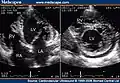

Trabeculation of the ventricles is normal, as are prominent, discrete muscular bundles greater than 2mm. In non-compaction there are excessively prominent trabeculations. Echocardiography is the reference standard for diagnosing NCC, although it can be well defined by computer tomography scan, positron emission tomography and magnetic resonance imaging.[13] Chin, et al., described echocardiographic method to distinguish non-compaction from normal trabeculation. They described a ratio of the distance from the trough and peak, of the trabeculations, to the epicardial surface.[14] Non-compaction is diagnosed when the trabeculations are more than twice the thickness of the underlying ventricular wall.